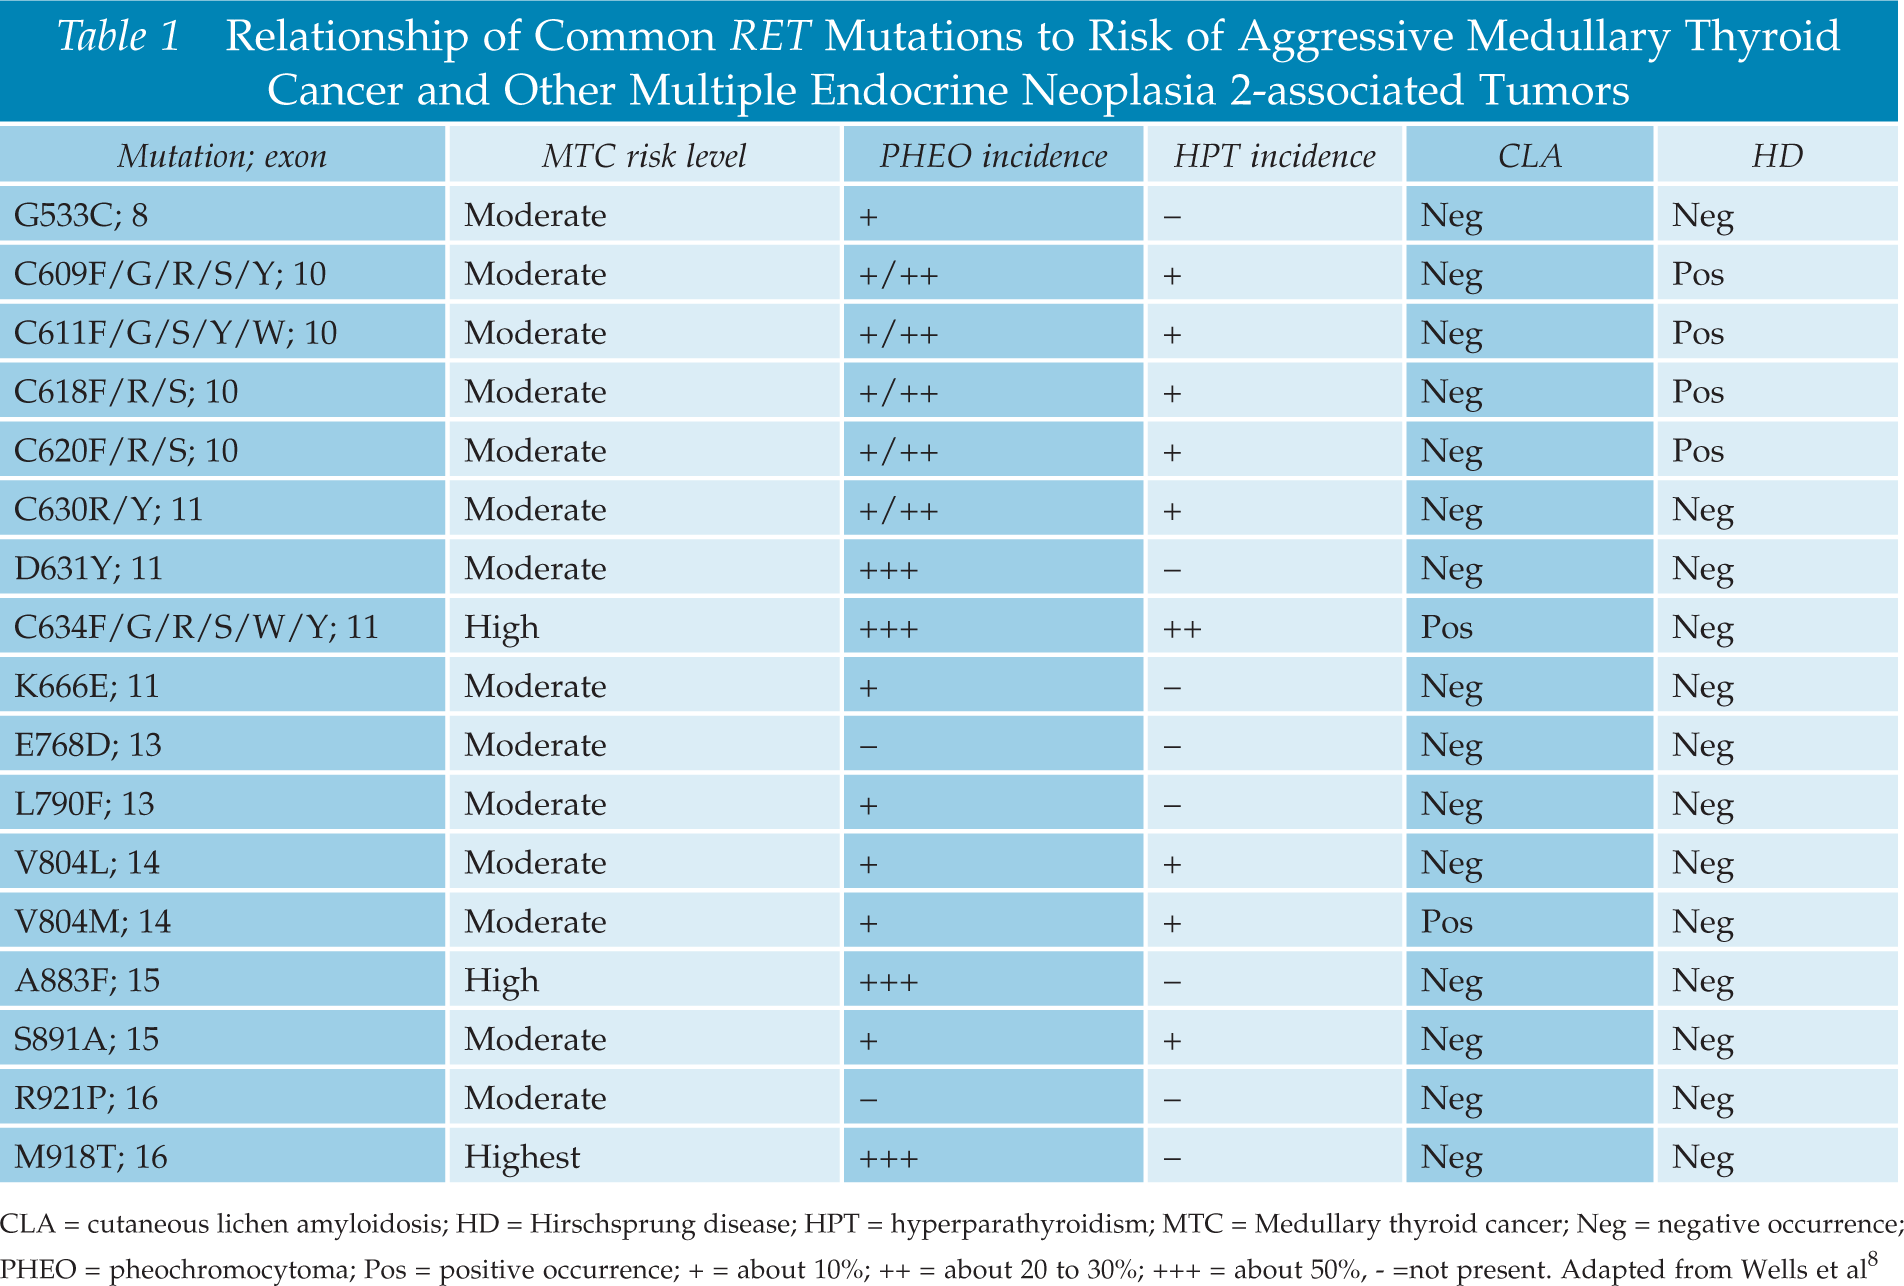

MTC is likely to run in families (inherited forms) in up to 25% of diagnoses, and inherited forms can be associated with other endocrine tumors, in syndromes called Multiple Endocrine Neoplasia (MEN) 2A and MEN 2B.

- In addition to MTC, patients with MEN2A may have tumors of the adrenal glands called pheochromocytomas or in the parathyroid glands (parathyroid adenomas). Patients with MEN2B, have MTC, pheochromocytomas and neuromas (typically a benign growth or tumor of nerve tissue) in the lining of the mouth and/ or gastrointestinal track.

- Patients with an inherited form of MTC usually have a mutation in a gene called the RET proto-oncogene. This mutation is present in all of the cells in their body (a germline mutation) and these mutations cause the development of MTC. This is important because in family members of a person with an inherited form of MTC, a blood test for a mutation in the RET protooncogene can lead to an early diagnosis of MTC and, to curative surgery to remove it. However, in the majority of patients (~ 75%) a germline mutation is not found – indicating that MTC is not an inherited or inheritable condition. In these cases, MTC is called sporadic.

Whether MTC is sporadic or familial can be determined by a blood test for the RET protooncogene. Anyone diagnosed with MTC should have this test run to determine whether the MTC is familial (meaning other family members may also have MTC that has not yet been diagnosed) or sporadic.

The RET proto-oncogene is located on chromosome 10. A genetic mutation in the RET oncogene is seen in all cells in the body in patients with the hereditary forms of MTC. Mutations in RET can also be seen only in the tumor cells in patients with sporadic MTC. Since the discovery of the RET oncogene, more than 100 different mutations have been identified in the gene in patients with MTC.

Genetic counseling and testing for RET gene mutations should be offered to patients diagnosed with MTC and first-degree relatives (parents, siblings and children of someone diagnosed with MTC) of all patients with proven germline mutations (hereditary MTC). If close relatives, especially children, are found to have the RET mutation on a blood test, the thyroid gland can be removed before MTC has a chance to develop or at least in its very early stages.